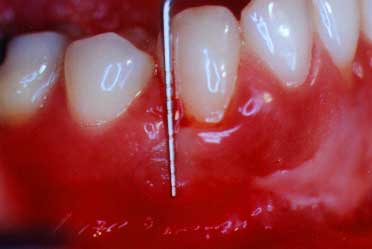

periodontal probe

The Periodontal Probe

This print shows the probe outside of the gum "sulcus" in order to show just how deep it would have gone (2-3 mm) in this healthy "sulcus"